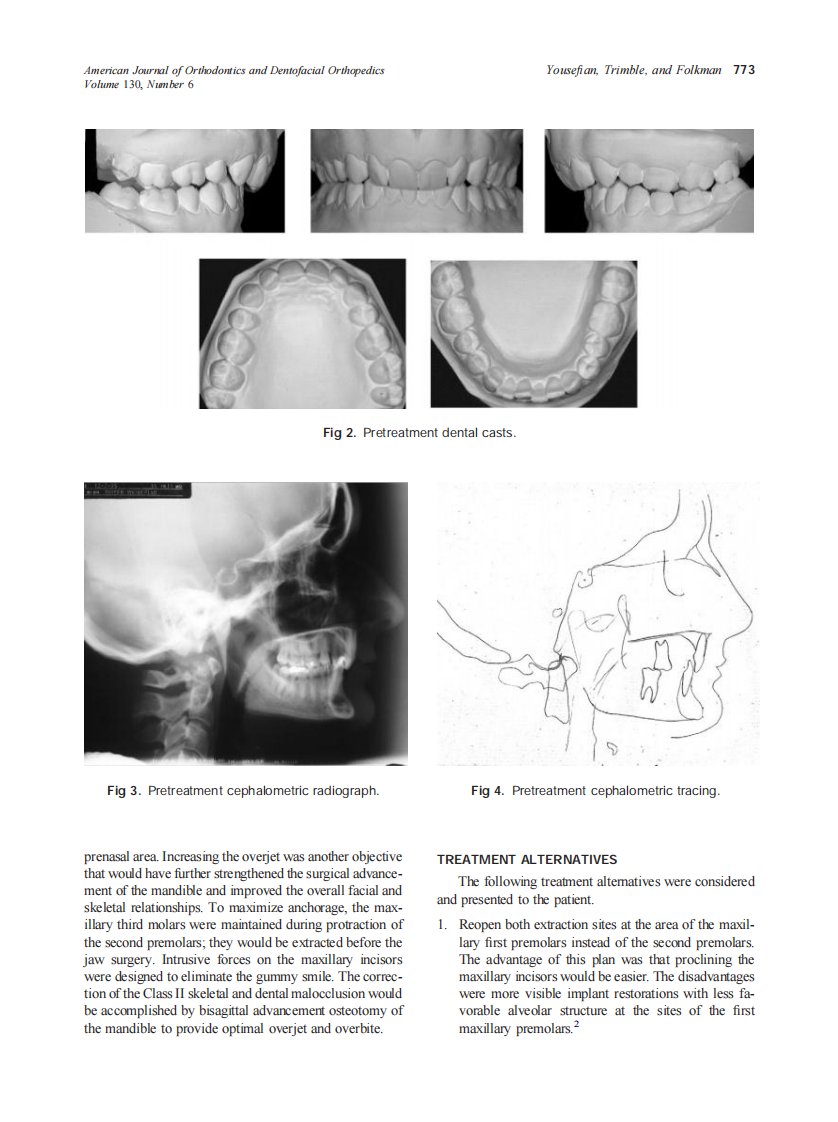

2006_130_6_771_778_Yousefian.pdf